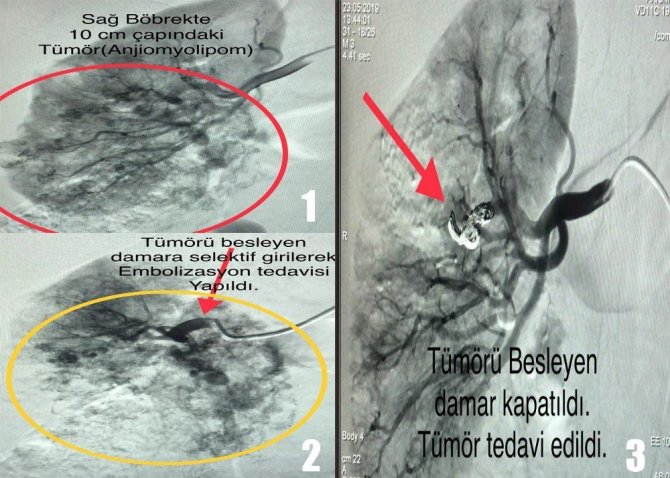

Kütahya Sağlık Bilimleri Üniversitesi (KSBÜ) Evliya Çelebi Eğitim ve Araştırma Hastanesi Girişimsel Radyoloji Bölümü’nde 10 cm çapında dev böbrek tümörü olan K.K. isimli kadın hastanın tümörü anjiografi ile embolizasyon (damar tıkama) yöntemiyle ameliyat yapılmadan 30 dakikada temizlendi.

Bu işlem bazı organ ve doku kanserlerinde kullanılmaktadır. Önce hastanın bu tedaviden fayda görüp görmeyeceği araştırılır. Uygun hastalarda anjiyografi (damar görüntüleme) cihazı ile tümörü besleyen damar görüntülenir. Ardından embolizasyon denilen işlem ile tümöre giden damar tıkatılır. Böylelikle tümör kanla beslenemez hale gelir, küçülüp yok olur.